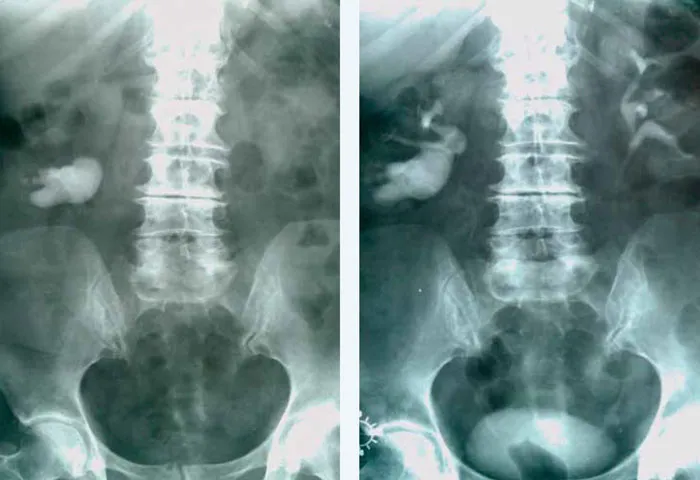

- Tomografia komputerowa (TK): Najdokładniejsza metoda diagnostyczna do wykrywania złogów, ich wielkości, lokalizacji i twardości. Jest szczególnie przydatna w planowaniu leczenia.

- RTG przeglądowe jamy brzusznej: Może wykryć kamienie wapniowe, które są widoczne na zdjęciu rentgenowskim.

- Urografia: Badanie rentgenowskie z kontrastem, które pozwala ocenić drożność dróg moczowych i funkcjonowanie nerek.